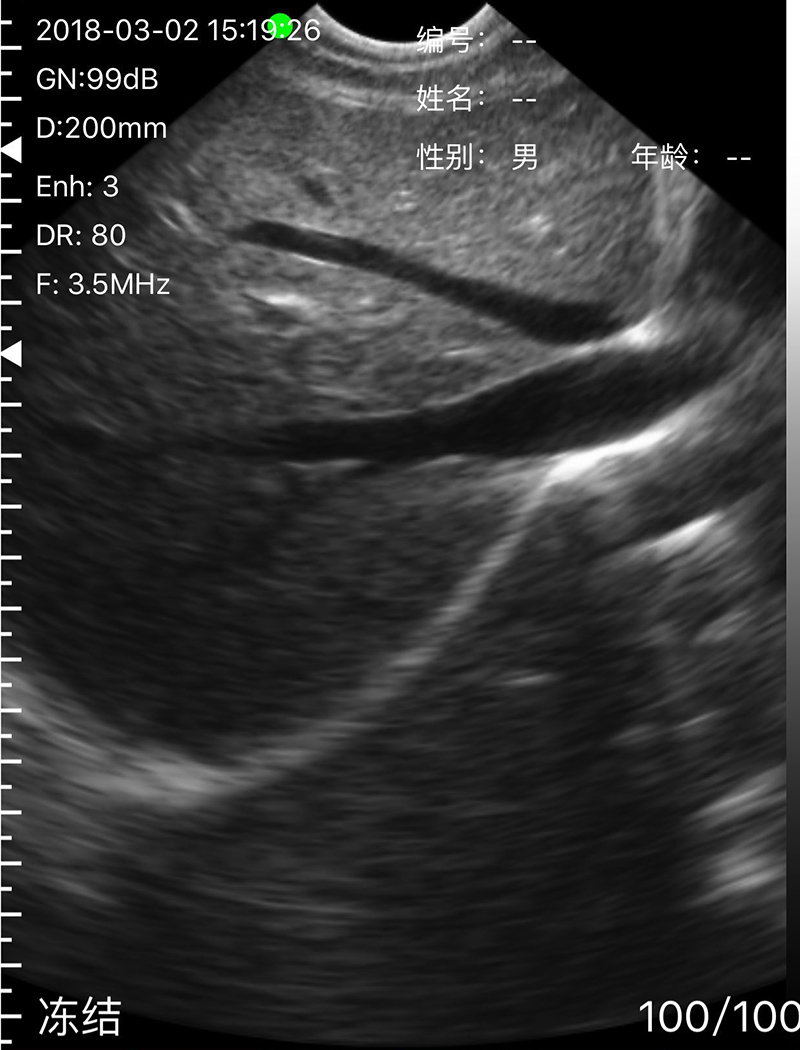

• 穿刺辅助功能:平面内穿刺引导线功能,平面外穿刺引导与血管自动测量功能,针尖显影增强功能